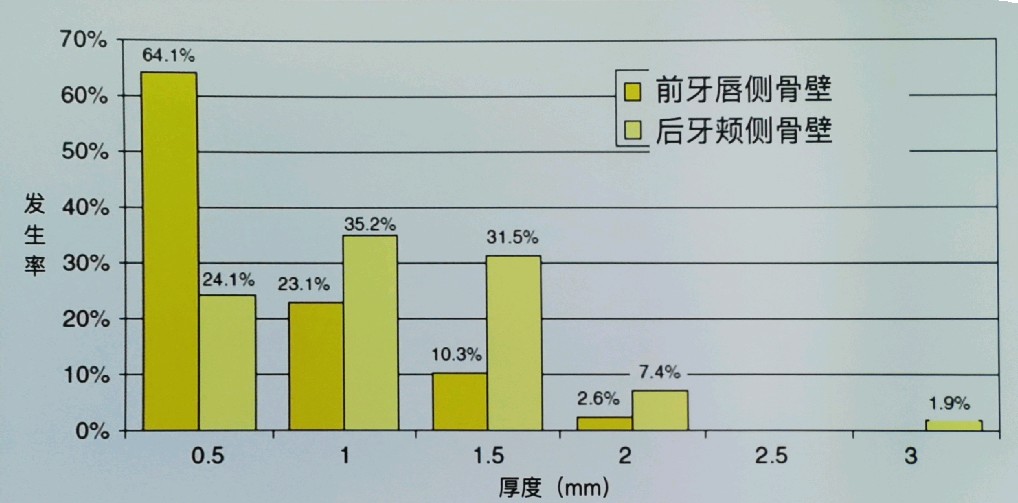

7.如不早期种植:常规90%唇侧骨板3个月吸收7mm失去最佳种植时机。(骨缺失后:如需种植先行复杂骨增量:取下颌骨、鼻底取骨,外斜线取骨,种植周种周期1-1.5年。)